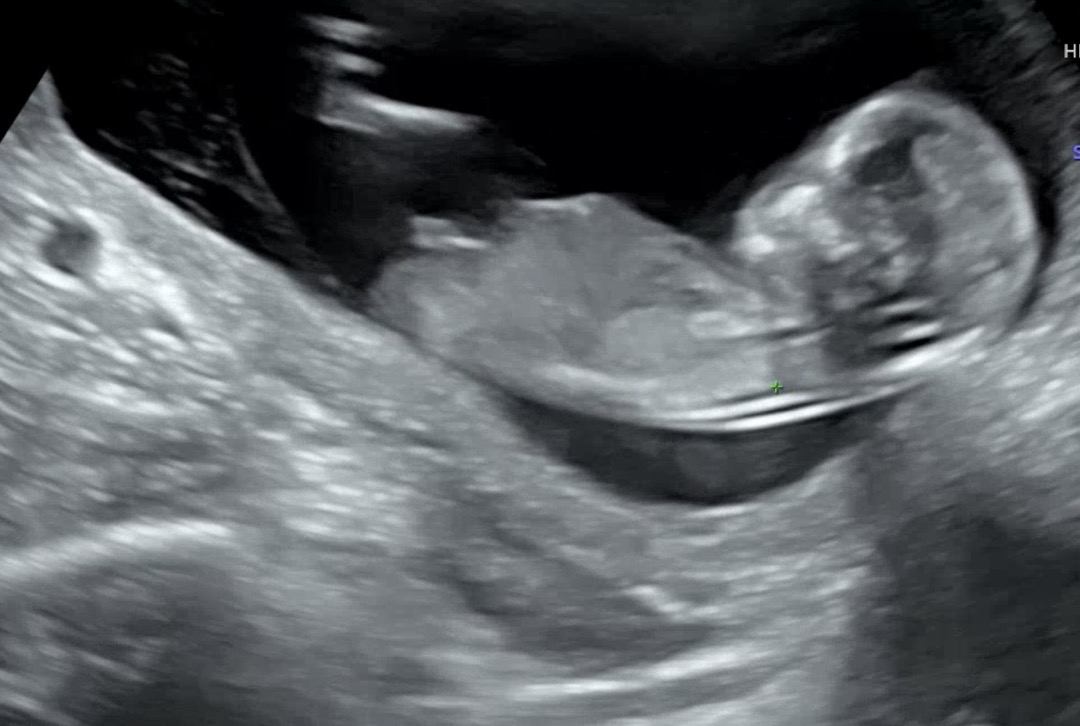

13주1일차 각도법 추측 부탁드려요!!

끝이 갈라져보이는거같기도하고..아들일까요 딸일까요??